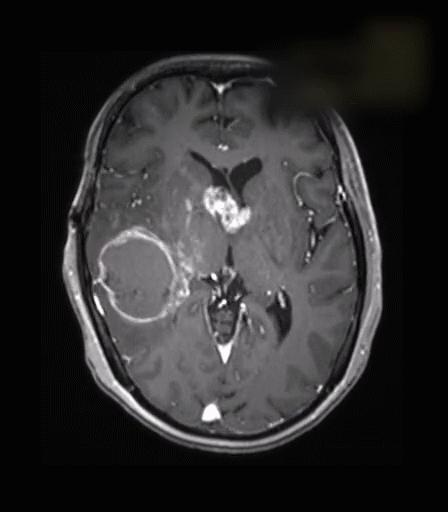

四级胶质瘤影像图

一个20岁花季大学生,恰风华正茂的美好年纪,一开始被诊断为胶质瘤二级,因为症状较轻没有认真对待,于是一等再等,谁知道,短短半年后,他的脑瘤迅速增大且恶化成了高级别,不仅头痛、呕吐症状十分严重,刚开始可能手术切除就能获得良好预后,现在除了手术,还要接受一些辅助放化疗手段进行治疗……此时的一家人开始后悔,早点手术积极治疗情况就不会这么复杂了

1 胶质瘤

恶化几率: 低级别胶质瘤生长缓慢,有文献报道一般每年生长2.2-5.5mm,经过约4-5年的静止期之后,恶性转化进入快速增长期,产生明显的神经系统症状变为高级别胶质瘤。低级别胶质瘤恶性转化的发生率据报道为21%,对于一些特别类型胶质瘤如少突胶质瘤恶化可能性就更高些,具体因素可能包括高龄、男性、多发性肿瘤位置以及切除不干净等等。

治疗策略: 胶质瘤最有效的治疗方案是手术为主、辅以放疗、化疗的综合治疗。手术主张保留患者神经功能状态下安全、最大范围地切除肿瘤。低级别的放化疗目前仍有很多争议,需要根据不同危险因素采取不同的治疗策略方案,但是争取彻底的根治性切除手术是最行之有效的治疗方法和保证预后的最关键因素。

最佳手术时机: 一般情况下患有胶质瘤病人一经发现尽早手术,推迟手术时,肿瘤会累及更多重要结构,增加手术难度和并发症的可能。肿瘤较大或有广泛的神经系统症状者,通常需要立即手术切除肿瘤。肿瘤较小以及症状轻微的病人,究竟是立即切除还是延迟手术,仍存在争议。很多研究者倾向于在确诊为低级别胶质瘤后,做安全范围内的最大切除能够提高患者的生存期。